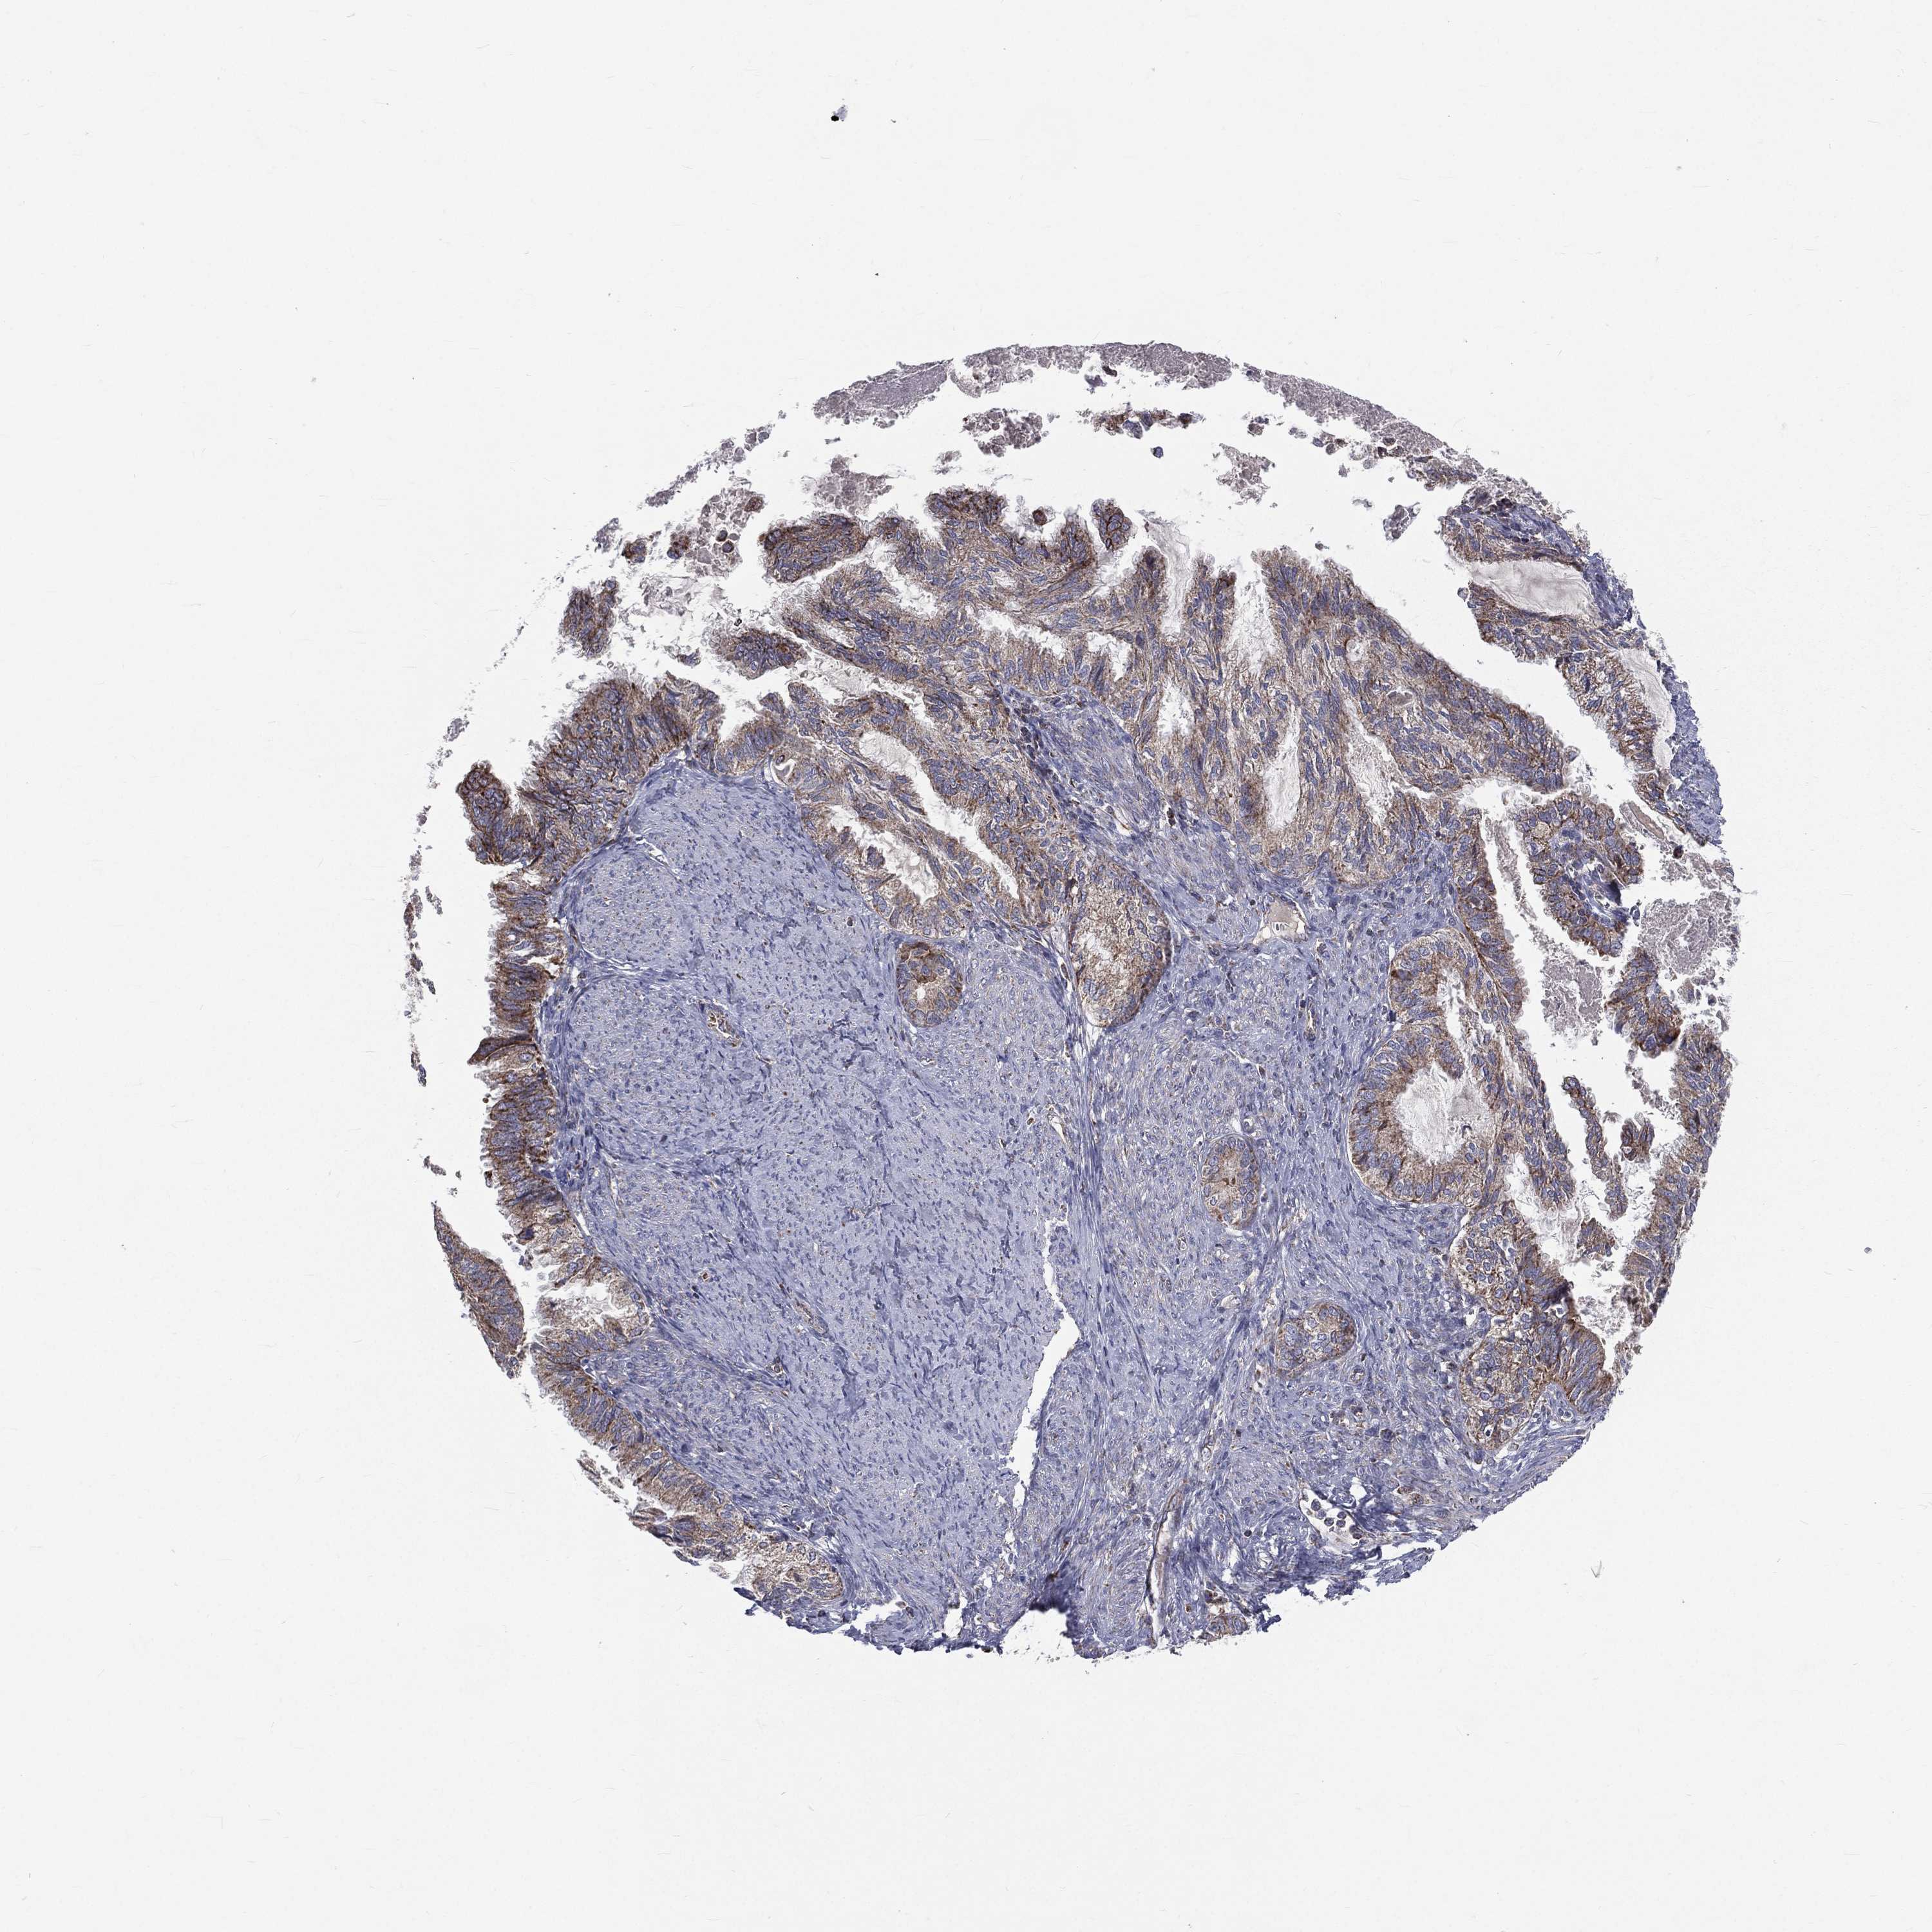

ENDOMETRIAL CANCER - Protein expressioni

A mouse-over function shows sample information and annotation data. Click on an image to view it in a full screen mode. Samples can be filtered based on level of antibody staining by selecting one or several of the following categories: high, medium, low and not detected. The assay and annotation is described here.

Note that samples used for immunohistochemistry by the Human Protein Atlas do not correspond to samples in the TCGA dataset.

Antibody stainingi

Antibody staining in the annotated cell types in the current human tissue is reported as not detected, low, medium, or high, based on conventional immunohistochemistry profiling in selected tissues. This score is based on the combination of the staining intensity and fraction of stained cells.

Each image is clickable and will lead to virtual microscopy that enables deeper exploration of all samples and also displays staining intensity scores, fraction scores and subcellular localization as well as patient and tissue information for each sample.

Antibody HPA044620

Antibody HPA058621

Staining

High

Medium

Low

Not detected

Intensity

Strong

Moderate

Weak

Negative

Quantity

>75%

75%-25%

<25%

None

Location

Nuclear

Cytoplasmic/membranous

Cytoplasmic/membranous,nuclear

Adenocarcinoma, NOS